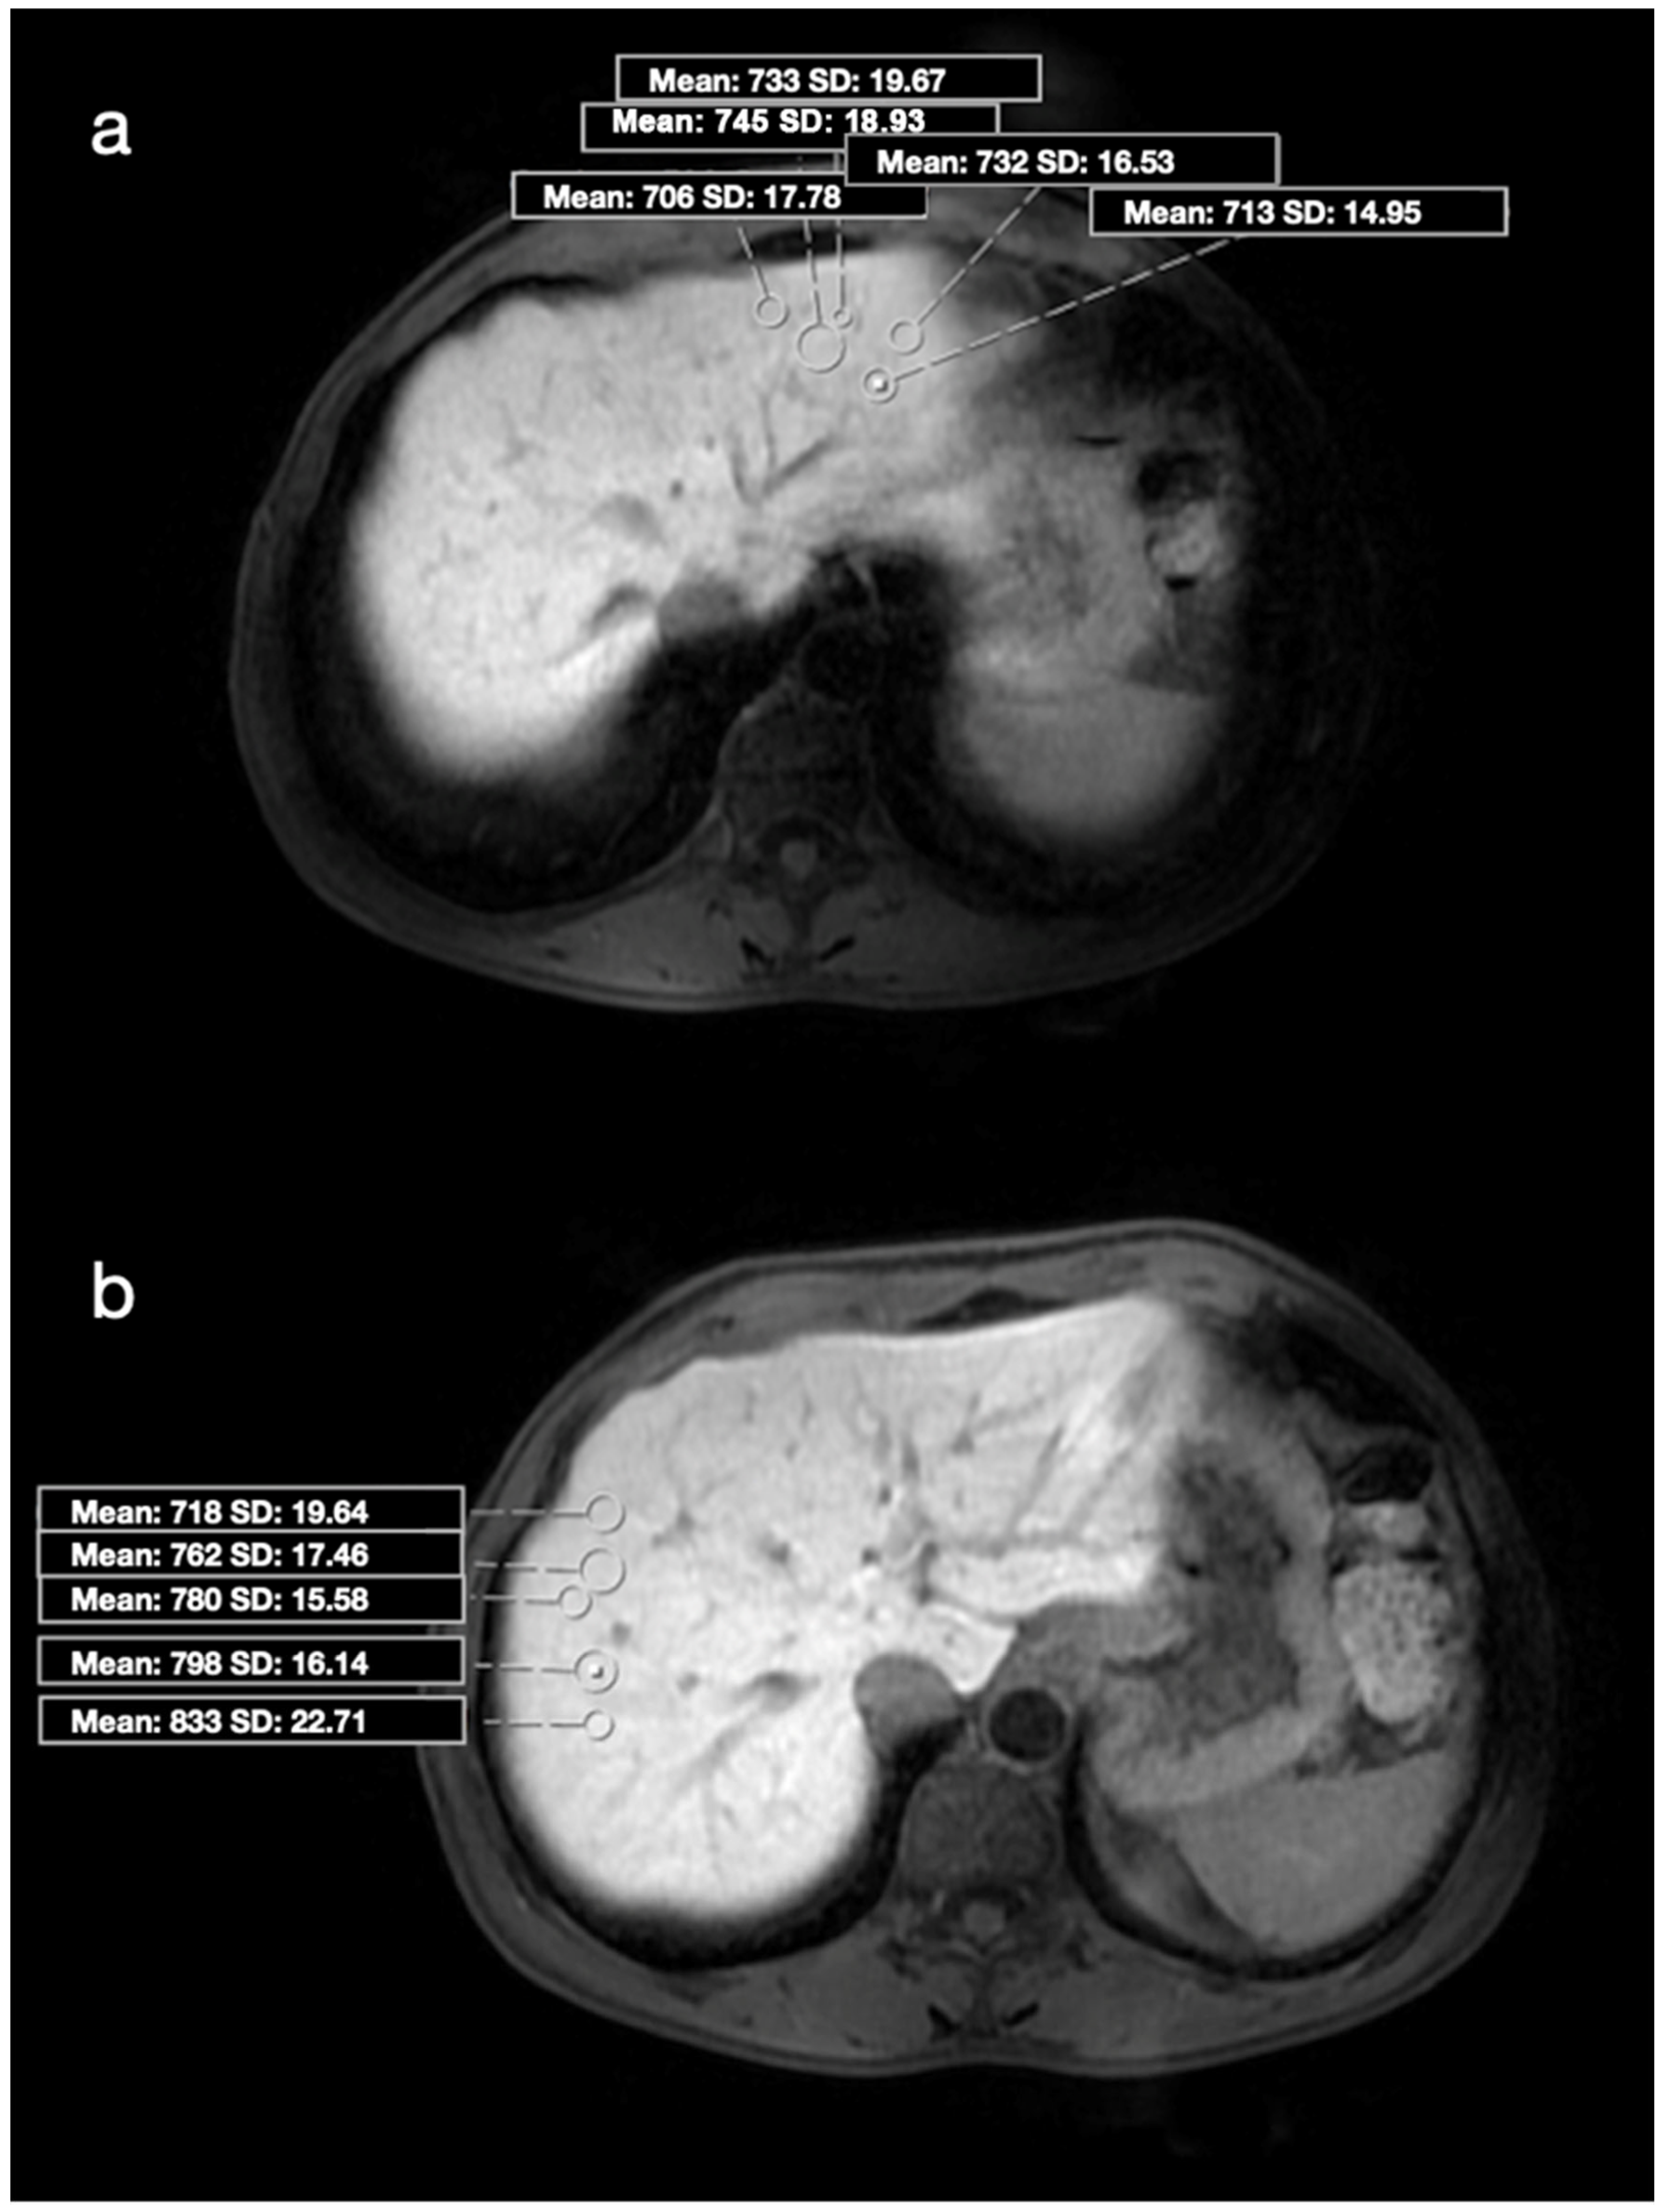

2.2. Image Analysis and Biopsy Procedure

| SI, mean (range) | 710.1 ± 231.9 (323–1592) | 573.2 ± 175.4 (161–1095) | 0.004 |

| SI, mean | 489.5 ± 100.6 | 793.8 ± 191.1 | <0.001 |